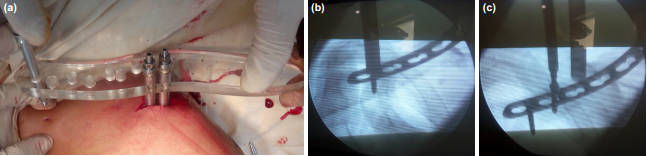

1、锁骨MIPO:微创钢板接骨术。

2、插入导向器组装的接骨板。(B)沿着锁骨上边缘插入接骨板

3、植入锁定螺钉